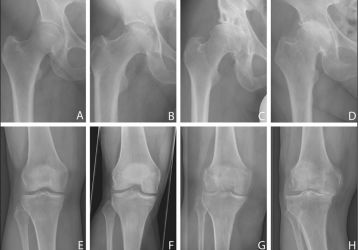

Болезнь Кенига или рассекающий остеохондрит коленного сустава: причины, симптомы и лечение

Что такое болезнь Кенига коленного сустава, причины развития патологии и характерные симптомы. Методы лечения рассекающего остеохондрита, профилактика.